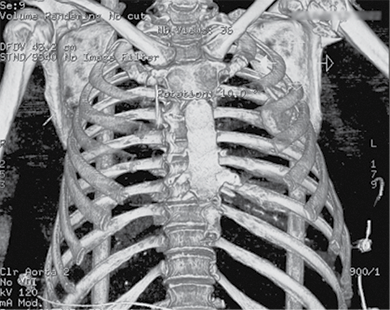

A 58-year-old patient was admitted to the Emergency Department of level I Trauma Center in August 2022 due to polytrauma sustained in a car accident. On arrival, the patient’s condition was severe, with decreased consciousness (GCS score of 12), unstable hemodynamic, subcompensated peripheral circulation, blood pressure of 62/32, and heart rate of 78 beats per minute. There was reduced breathing on the left side with a respiratory rate of 18 breaths per minute and an oxygen saturation (SpO2) of 85.0%. Palpation revealed pain in the left posterior chest. X-rays and CT scans were performed, which revealed a traumatic hemothorax on the left side, humeral head within the pleural cavity, three rib fractures, lung contusion, and hematoma.

Figure 1. First X-ray and computer tomography upon admission (with humeral head shown)